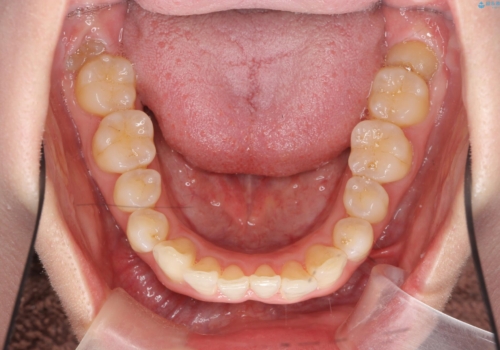

インビザライン で治す 出っ歯の治療

- 前歯の突出感、出っ歯の治療を希望され来院されました。

インビザラインを用いた治療計画を立て、しっかりと出っ歯を治すためにマイクロインプラントを併用します。

マイクロインプラントを併用することでしっかりとマウスピース全体を後方へ引き、前歯の突出感を改善することができました。